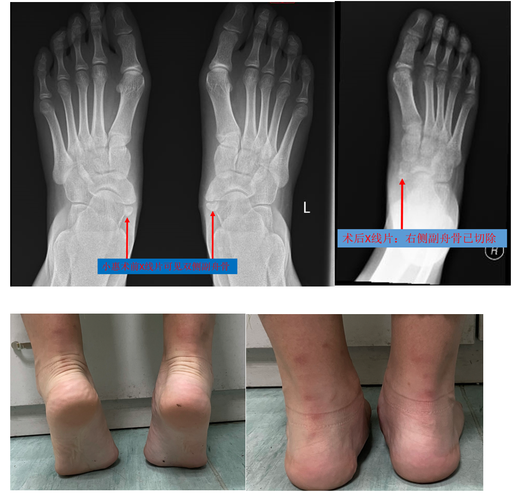

- 手术方案通常包括:切除引起症状的副舟骨、重新将胫后肌腱固定到正常的位置(肌腱移位术)、同时进行足弓的重建。